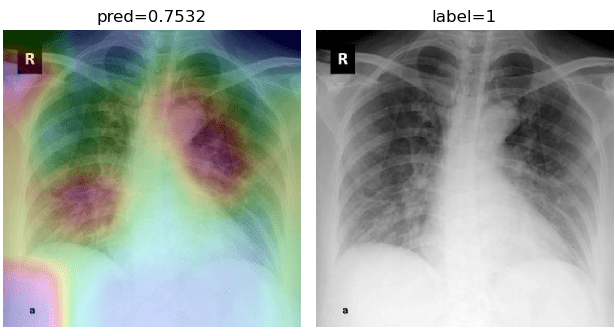

To overcome the aforementioned issues and force the model’s attention to the correct regions of interest (ROIs), we introduce the COVID-CXNet. Our model is initialized with the pretrained weights from CheXNet. A dataset of 3,628 images, 3,200 normal CXRs and 428 COVID-19 CXRs, are divided into 80% as training-set and 20% as test-set. Batch size is set to 16, rather than 32 in previous models, regarding memory constraints. Grad-CAMs of the COVID-CXNet for random images are plotted in Fig. 15.

Refer to caption

Figure 15: Grad-CAM visualization of the proposed model over sample cases

More Grad-CAMs are available in Appendix A. Heatmaps are more accurate than previous models, while an accuracy of 99.04% and an f-score of 0.96 are achieved. Table 3 is the confusion matrix of the proposed model.